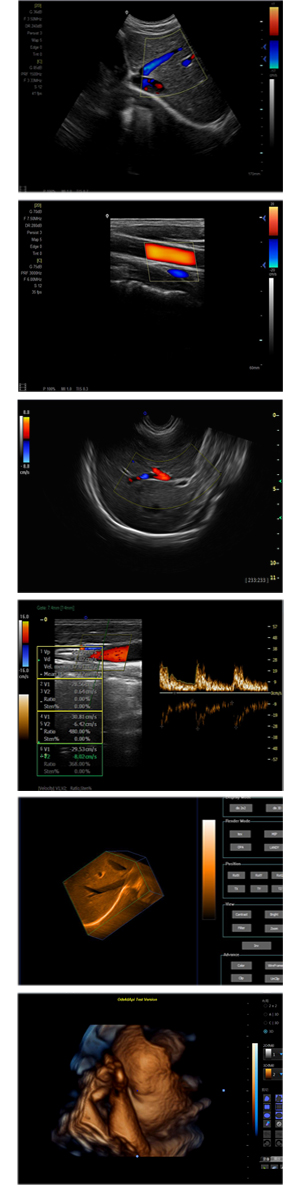

XF-7600型,秉承先鋒彩超技術之精華,擁有高雅大氣的獨特外型,為最新一代應用型數(shù)字彩色多普勒診斷系統(tǒng),魅力與實力相融合??蓮V泛適用于腹部、婦產(chǎn)科、心臟、小器官、乳腺、肌骨及外周血管等諸多方面的診查,讓您在臨床超聲診斷應用領域得心應手,綻放異彩!

突破的成像技術

● 3D/ 4D成像技術/選配

● 應用于腹部、腎臟、泌尿系統(tǒng)、產(chǎn)科、婦科、盆腔、大動脈、肌肉組織、小器官、乳腺、心臟等

● 能量多普勒成像(PDI)

● 彩色血流量圖(CDE)

● 脈沖頻譜多普勒成像(PW)